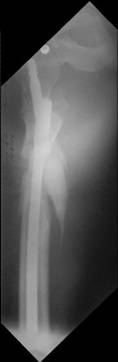

Few days ago I have posted an x-ray of severely comminuted Trochenteric # of Lt. Femur with sub-trochenteric extension of a male patient aged 65 years for opinion of fixation. Eight of you have kindly replied........

I choose Long Gamma Nailing and did it on 24.1.2006.

Now posting the post op x-rays for all of yours comments please. Don't hesitate to criticize me.

Congratulations. Virtually perfect. What reduction technique did you use? Looks like still traction table? To cavil to at least something looks like reduction is in microscopic varus - comparative x-rays can clear this - though only for academic interest with no clinical significance. Did you insert distal screws?